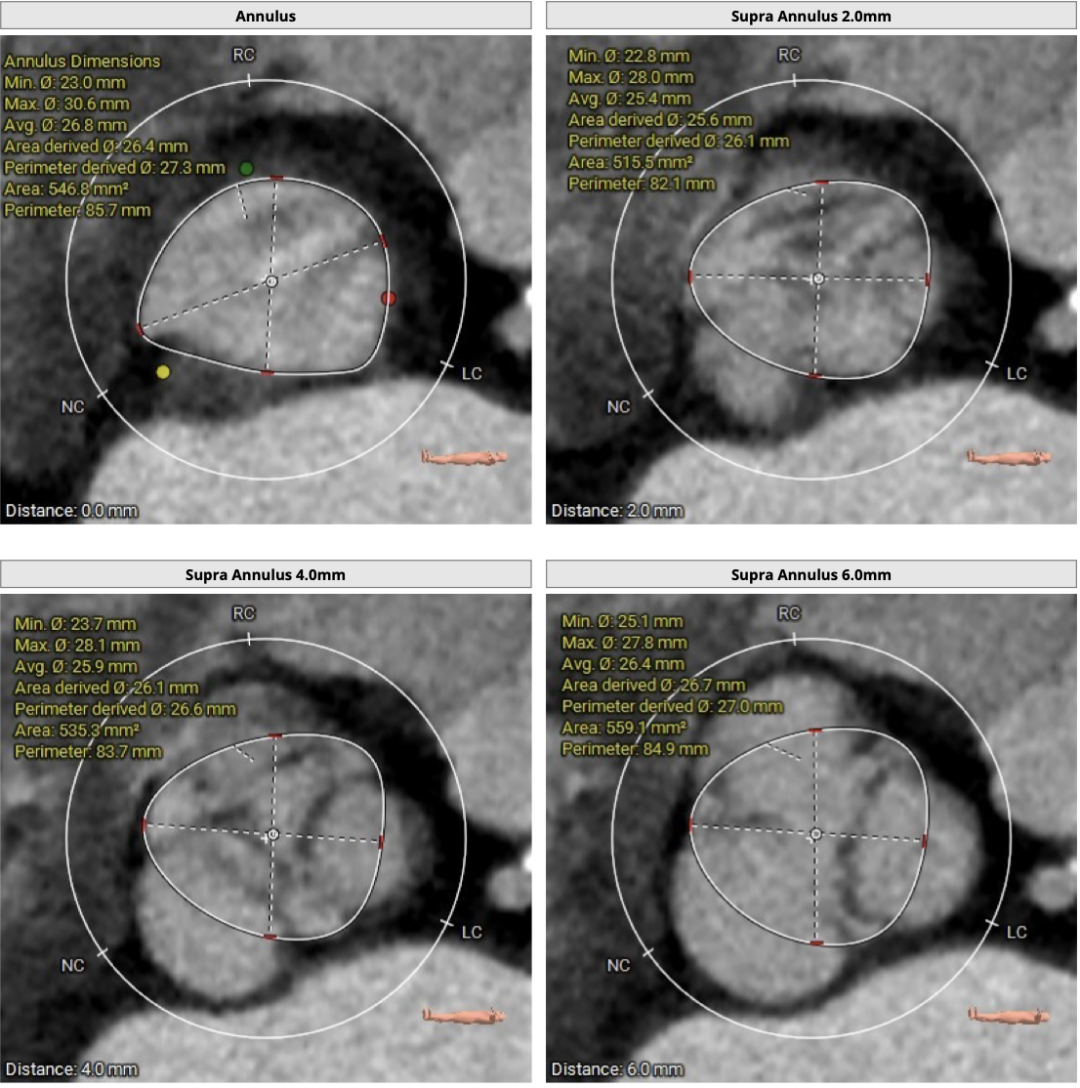

CT分析

患者主动脉瓣三叶式,瓣叶基本等大,瓣叶稍增厚,未见明显钙化;主动脉瓣环周长折算直径约27.3mm:

左室流出道凸出: